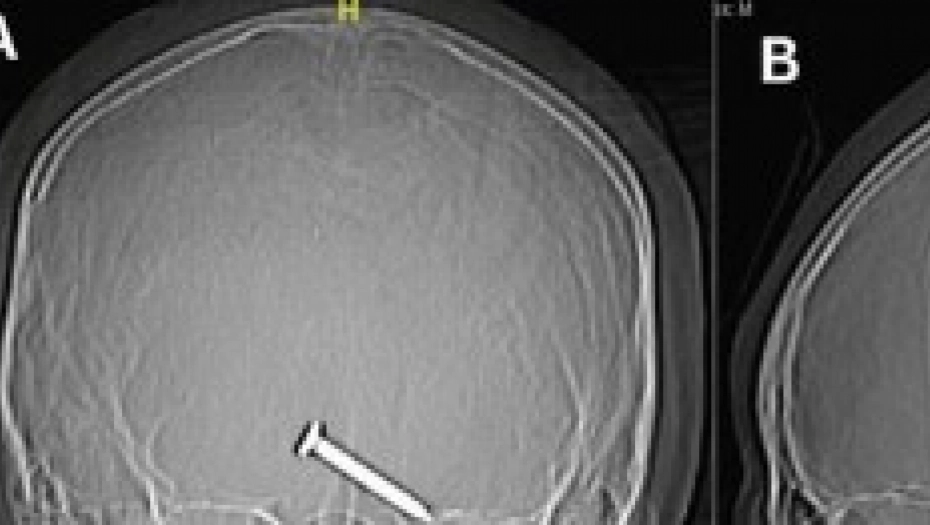

Tada je nehotično povukao oroz, a zašiljeno parče metala (dugačko tri centimetra) pogodilo ga je u glavu, prenosi Daily Mail.

Ispostavilo je da je ekser promašio očnu jabučicu za nekoliko milimetara i zabio se u prednji deo mozga, vitalan za funkcije kretanja i govora.